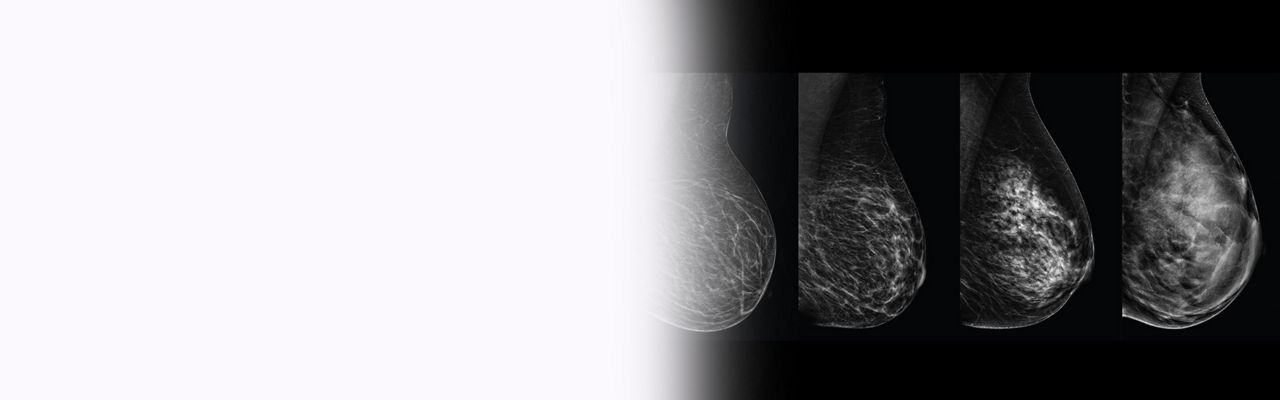

Why breast density matters

Dense breast tissue and cancer appear white on a mammogram, potentially camouflaging small cancers, and in fact, up to 50% of breast cancers may be missed in extremely dense breasts.⁴